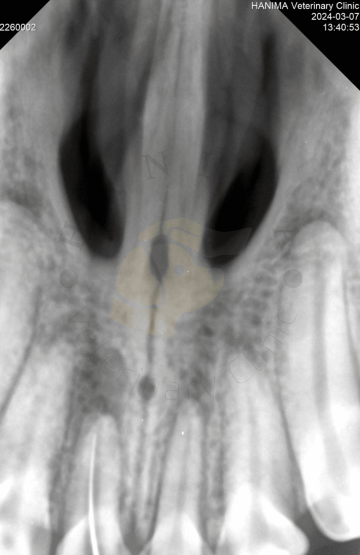

Když si pes zlomí zub a obnaží dřeň, bakterie a zbytky z úst proniknou do středu zubu. V důsledku toho se rozvine bolestivý zánět dřeně (pulpitida), který nakonec způsobí odumírání nervů a krevních cév (nekróza dřeně). Bakterie pronikají ven z kořenového hrotu (špička kořene obklopená kostí) a infikují kost kolem kořene (apikální parodontitida). Pulpitida i apikální parodontitida jsou velmi bolestivé. Vzhledem k tomu, že infekce zubu a následně také infekce kosti kolem kořene je vysoce pravděpodobná, zlomené zuby s obnažením dřeně by měly být co nejdříve ošetřeny buď standardní terapií kořenových kanálků tj. endodonticky, nebo extrakcí.